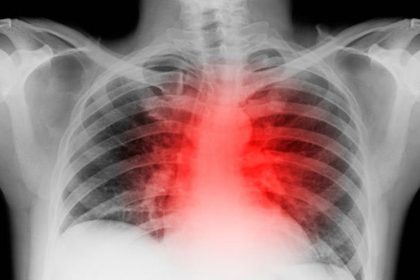

Viroza pulmonară: simptome și cum trebuie tratată corect

Viroza pulmonară sau viroza respiratorie este o infecție acută virală ușoară și autolimitata a tractului respirator superioar care determină simptome…